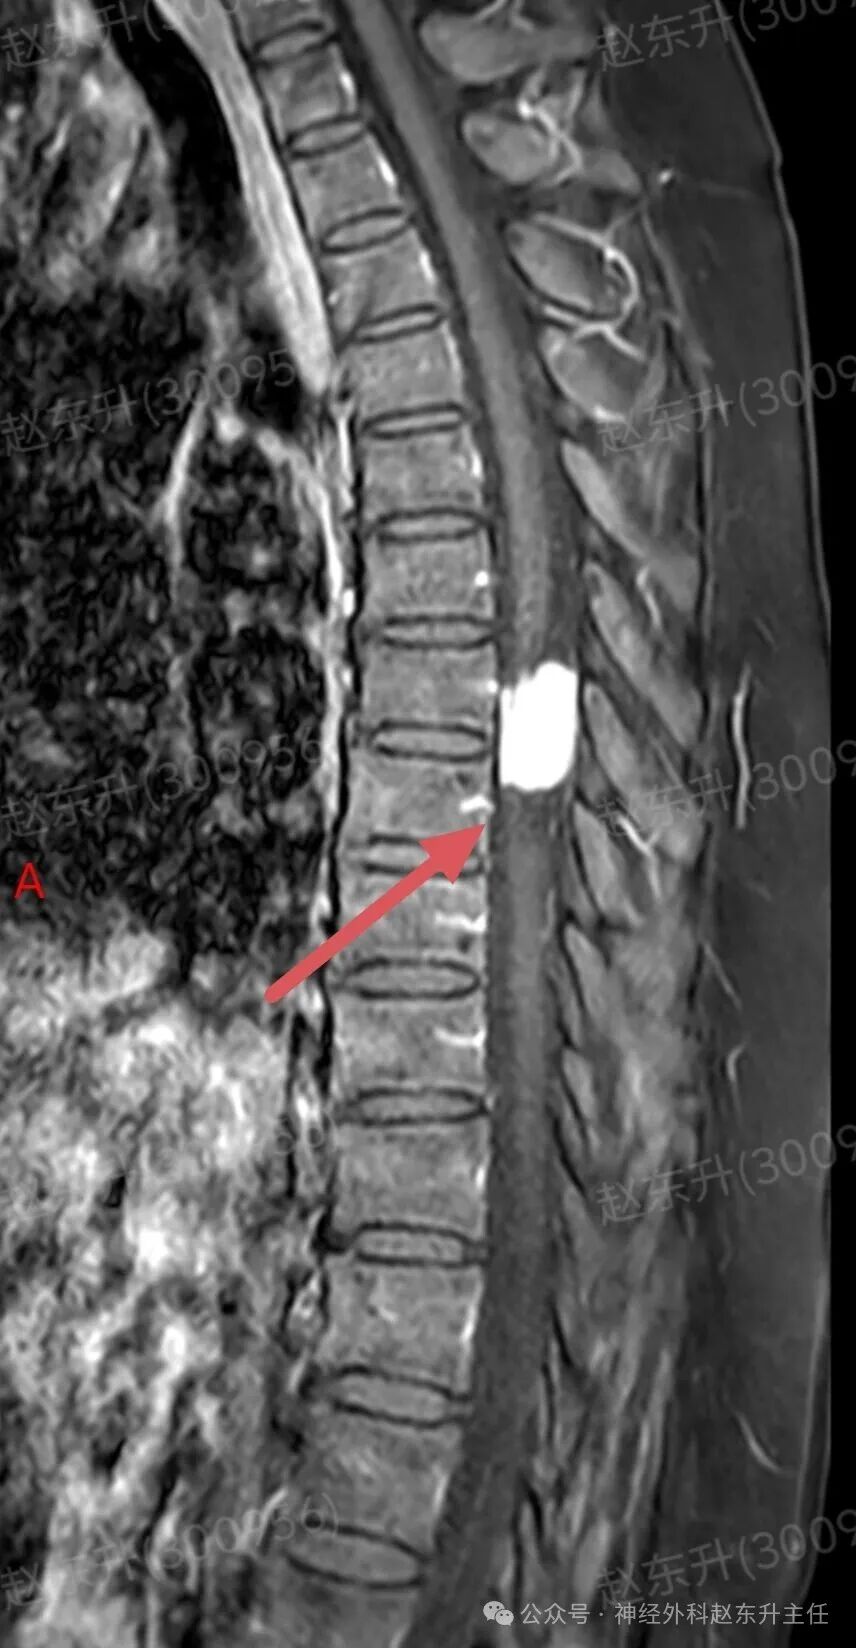

今天介绍一个58岁女性患者,因为腰部疼痛麻木伴双下肢麻木乏力半年入院的患者半年前开始出现下肢麻木乏力,但可独立行走。没有引起重视,逐渐症状加重,伴有腰部疼痛,夜间疼痛比较明显明显难以忍受,随后在当地医院查了ct和核磁共振发现椎管内一个巨大的肿瘤压迫脊髓。当地医院不敢手术,因为患者虽然疼痛麻木,疼痛评分有10分,但可以行走。随后他到西安市红会医院神经外科找到了赵东升主任,经过详细的术前评估和检查以后在全麻下显微镜下进行了肿瘤全切术后患者疼痛立即减轻,术后第2天开始做经颅磁刺激等神经康复治疗。术后一周就可以下地行走了,大小便也恢复了正常。患者感激到终于有人帮我解决了这个折磨他半年的一个疾病。

磁共振成像:是首选和确诊性检查。典型表现:T1加权像呈等或稍低信号,T2加权像呈等或稍高信号;增强扫描后呈现均匀、显著的强化,可见特征性的“硬膜尾征”(邻近硬脊膜线状强化)。